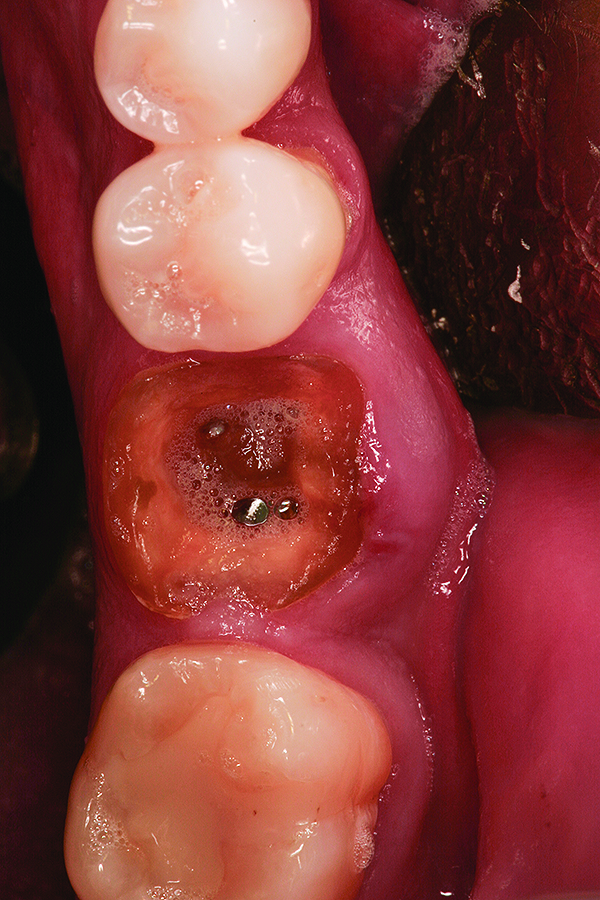

Fig 12. Note the significant formation of bone and repair of the buccal osseous defect at 3 months healing.

Figure 12

Fig 13. Placement of dental implant into healed bone. Note complete circumferential bone surrounding all aspects of the dental implant.

Figure 13